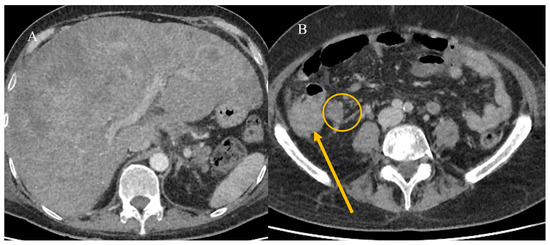

2.7. Metastatic Presentation of Small Bowel Tumors